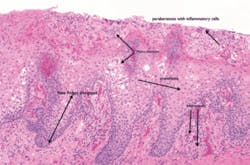

Significant microscopic characteristics: Micro abscesses are microscopically diagnostic of geographic tongue (called abscesses of Munro), inflammatory cells, and obvious loss of the epithelial surface in areas of the clinically denuded patches. The histological appearance of geographic tongue is microscopically similar to cutaneous psoriasis (see Figure 6).